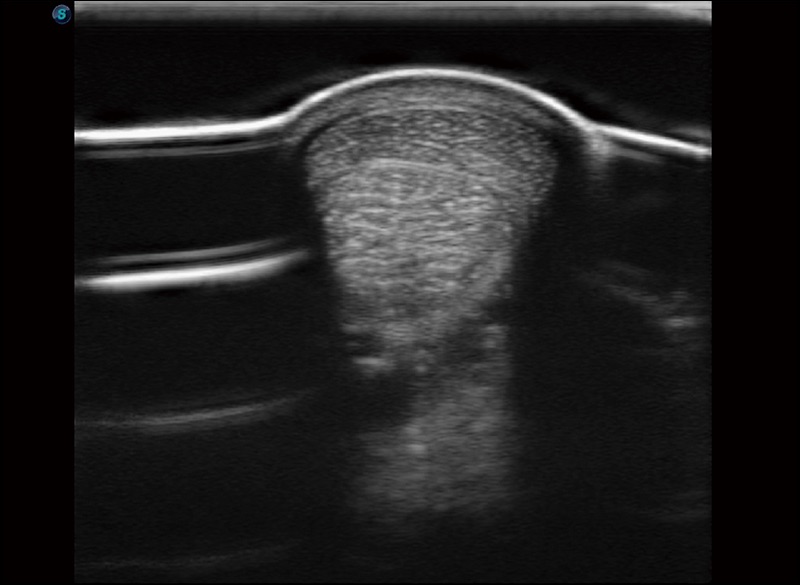

穿刺针增强

高清显示穿刺进针情况

临床图